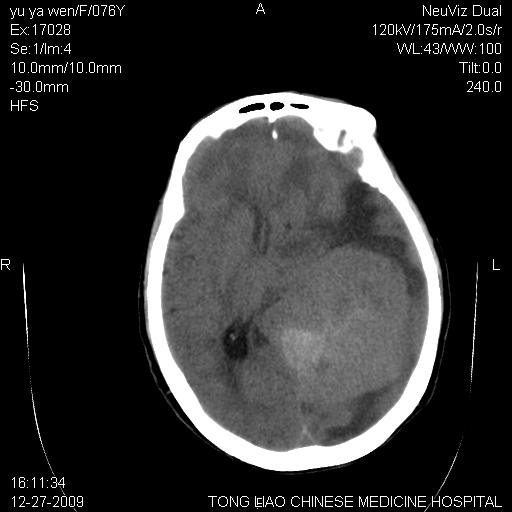

以下是引用lizhiguang在2009-12-27 19:06:00的发言:[br]脑膜瘤

以下是引用zhao_bin2008在2009-12-27 20:34:00的发言:[br]考虑脑膜瘤,伴肿瘤出血,建议增强检查

以下是引用zsl6918在2009-12-27 19:28:00的发言:[br]建议对症治疗后强化检查,考虑脑膜瘤可能性大。